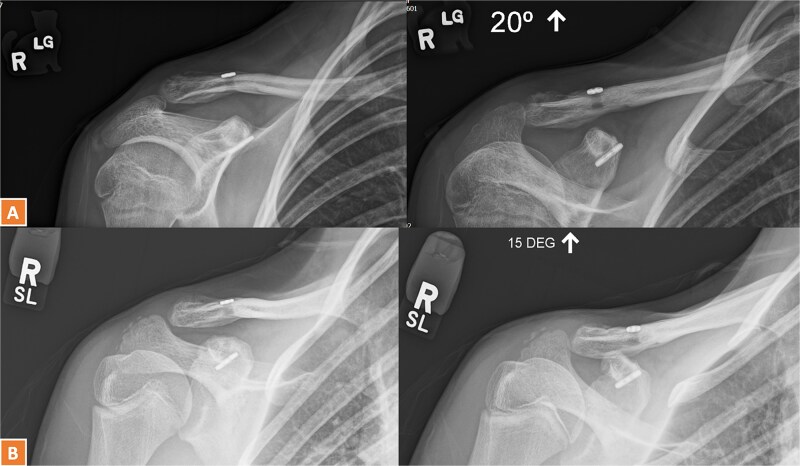

Lateral end clavicle fractures, especially those that are displaced, have a high rate of delayed and non-union. This case series presents three patients with unstable lateral end clavicle fractures successfully treated with TightRope fixation as the sole method of stabilization, demonstrating excellent functional outcomes and minimal complications. The comprehensive literature review reveals mounting evidence with eight reported studies supporting TightRope as an effective standalone treatment option, with the largest published series showing 79% union rates and only 10% complication rates. These findings, combined with the theoretical advantages of avoiding routine hardware removal, lower costs, and compatibility with day-surgery protocols, suggest that TightRope fixation merits serious consideration as a primary treatment modality for appropriately selected patients with lateral end clavicle fractures.

Abstract Image